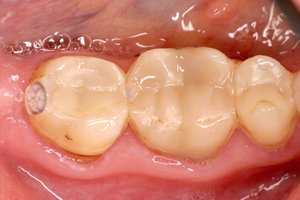

In deze lezing wordt dieper ingegaan op de verschillende stappen bij het plaatsen van de enkelvoudige posterieure composietrestauratie: de keuze van het composiet en adhesief systeem, de caviteitspreparatie, afzondering, het matrixsysteem, laagjes techniek versus bulk fill, vormgeving, occlusie en afwerking. Zowel de meer beperkte als uitgebreide posterieure composietrestauratie met knobbelopbouw komen aan bod. Tenslotte wordt belicht dat regelmatig onderhoud en lokaal herstel van de defecte posterieure composietrestauratie de levensduur zal verlengen.

Voorspelbare functie en esthetiek van de definitieve restauratie bij patiënten met een (ernstig) versleten dentitie vereist een gezamenlijke klinische en technische benadering door tandarts en tandtechnicus. Een systematisch concept bereik je door nauwkeurige behandelplanning met een diagnostische wax-up waarmee materiaalkeuze, preparatievorm, ‘soft-tissue management’ en tijdelijke voorzieningen worden bepaald. Tijdelijke voorzieningen spelen een essentiële rol in de communicatie tussen de patiënt en het behandelteam.